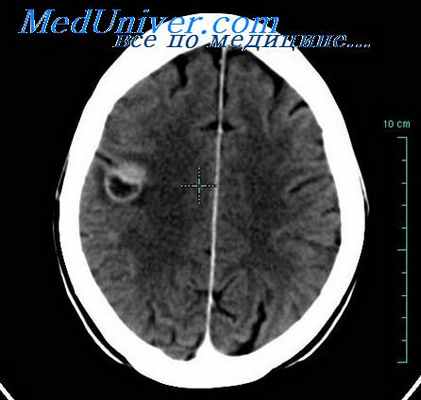

Рисунок 2. Как выглядит субарахноидальное кровоизлияние на диагностическом снимке. Источник:Brazilian Journal of Psychiatry (Creative Commons Attribution Non-Commercial License)

В классификации Фишера вид кровоизлияния оценивается по данным компьютерной томографии, в ней выделяется четыре группы:

- I группа – КТ не показывает наличие кровив субарахноидальном пространстве,

- II – диффузное кровоизлияние или сгустки крови в субарахноидальном пространстве толщиной до 1 мм,

- III – сгустки крови в субарахноидальном пространстве толщиной более 1 мм,

- IV – сгустки крови в субарахноидальном пространстве в сочетании с внутрижелудочковым или внутримозговым кровоизлиянием.